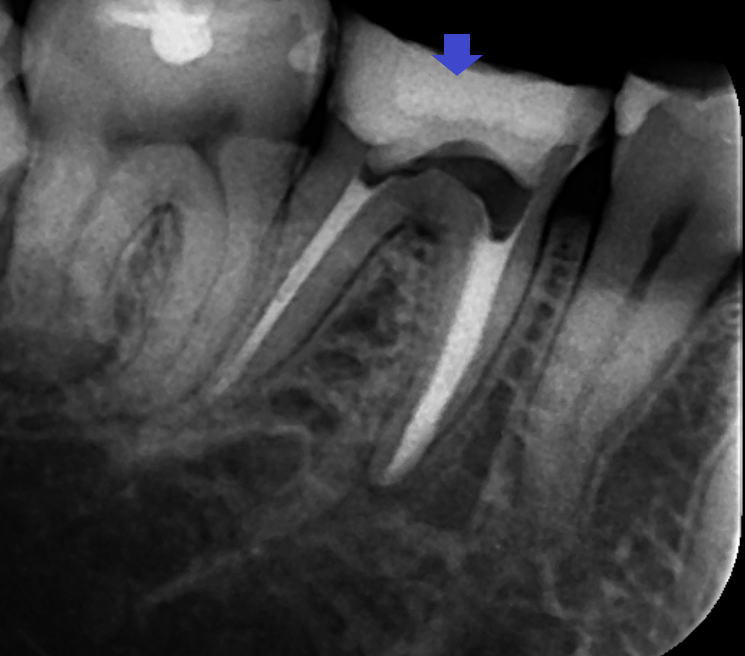

精密再根管治療を行い、近心根のイスムスを顕微鏡下で清掃しました。画像は、根管充填時のレントゲン写真です。